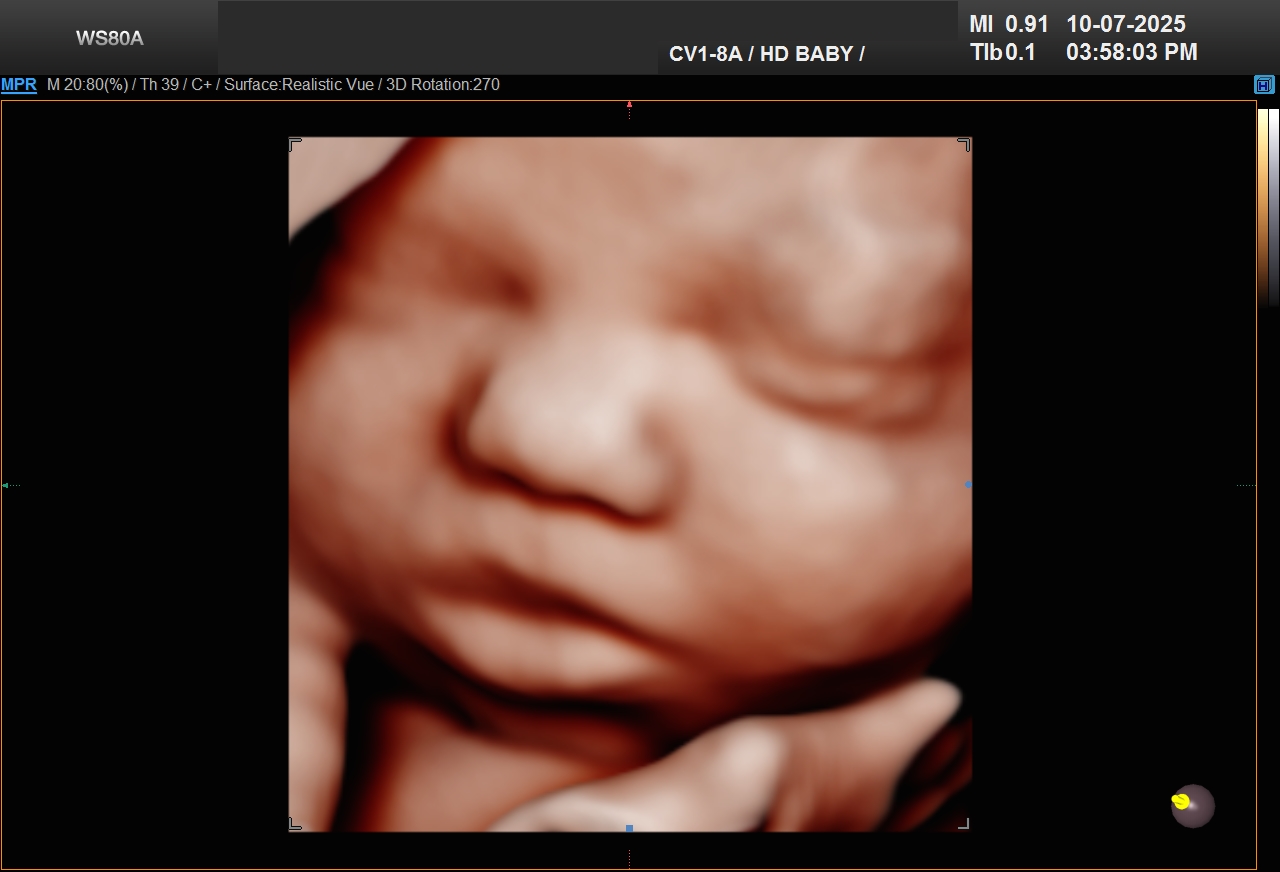

We are an elective ultrasound studio that specializes in early gender determination and High Definition ultrasounds.